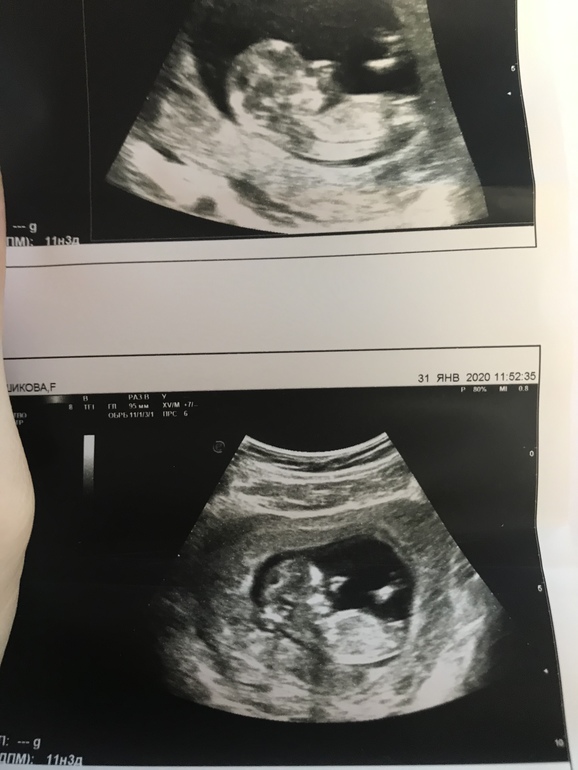

Узи 12 недель

БеременностьРешила сходить сегодня на узи, перед скринингом. Оказалось не зря, мы опережаем свой рост на 1,5 недели. С уверенностью в 80 % сказали девочка, крупненькая, и здоровая, все пальчик на месте, сердце развилось 4-х камерное, головка тоже в порядке. Моему счастью нет предела❤️😂